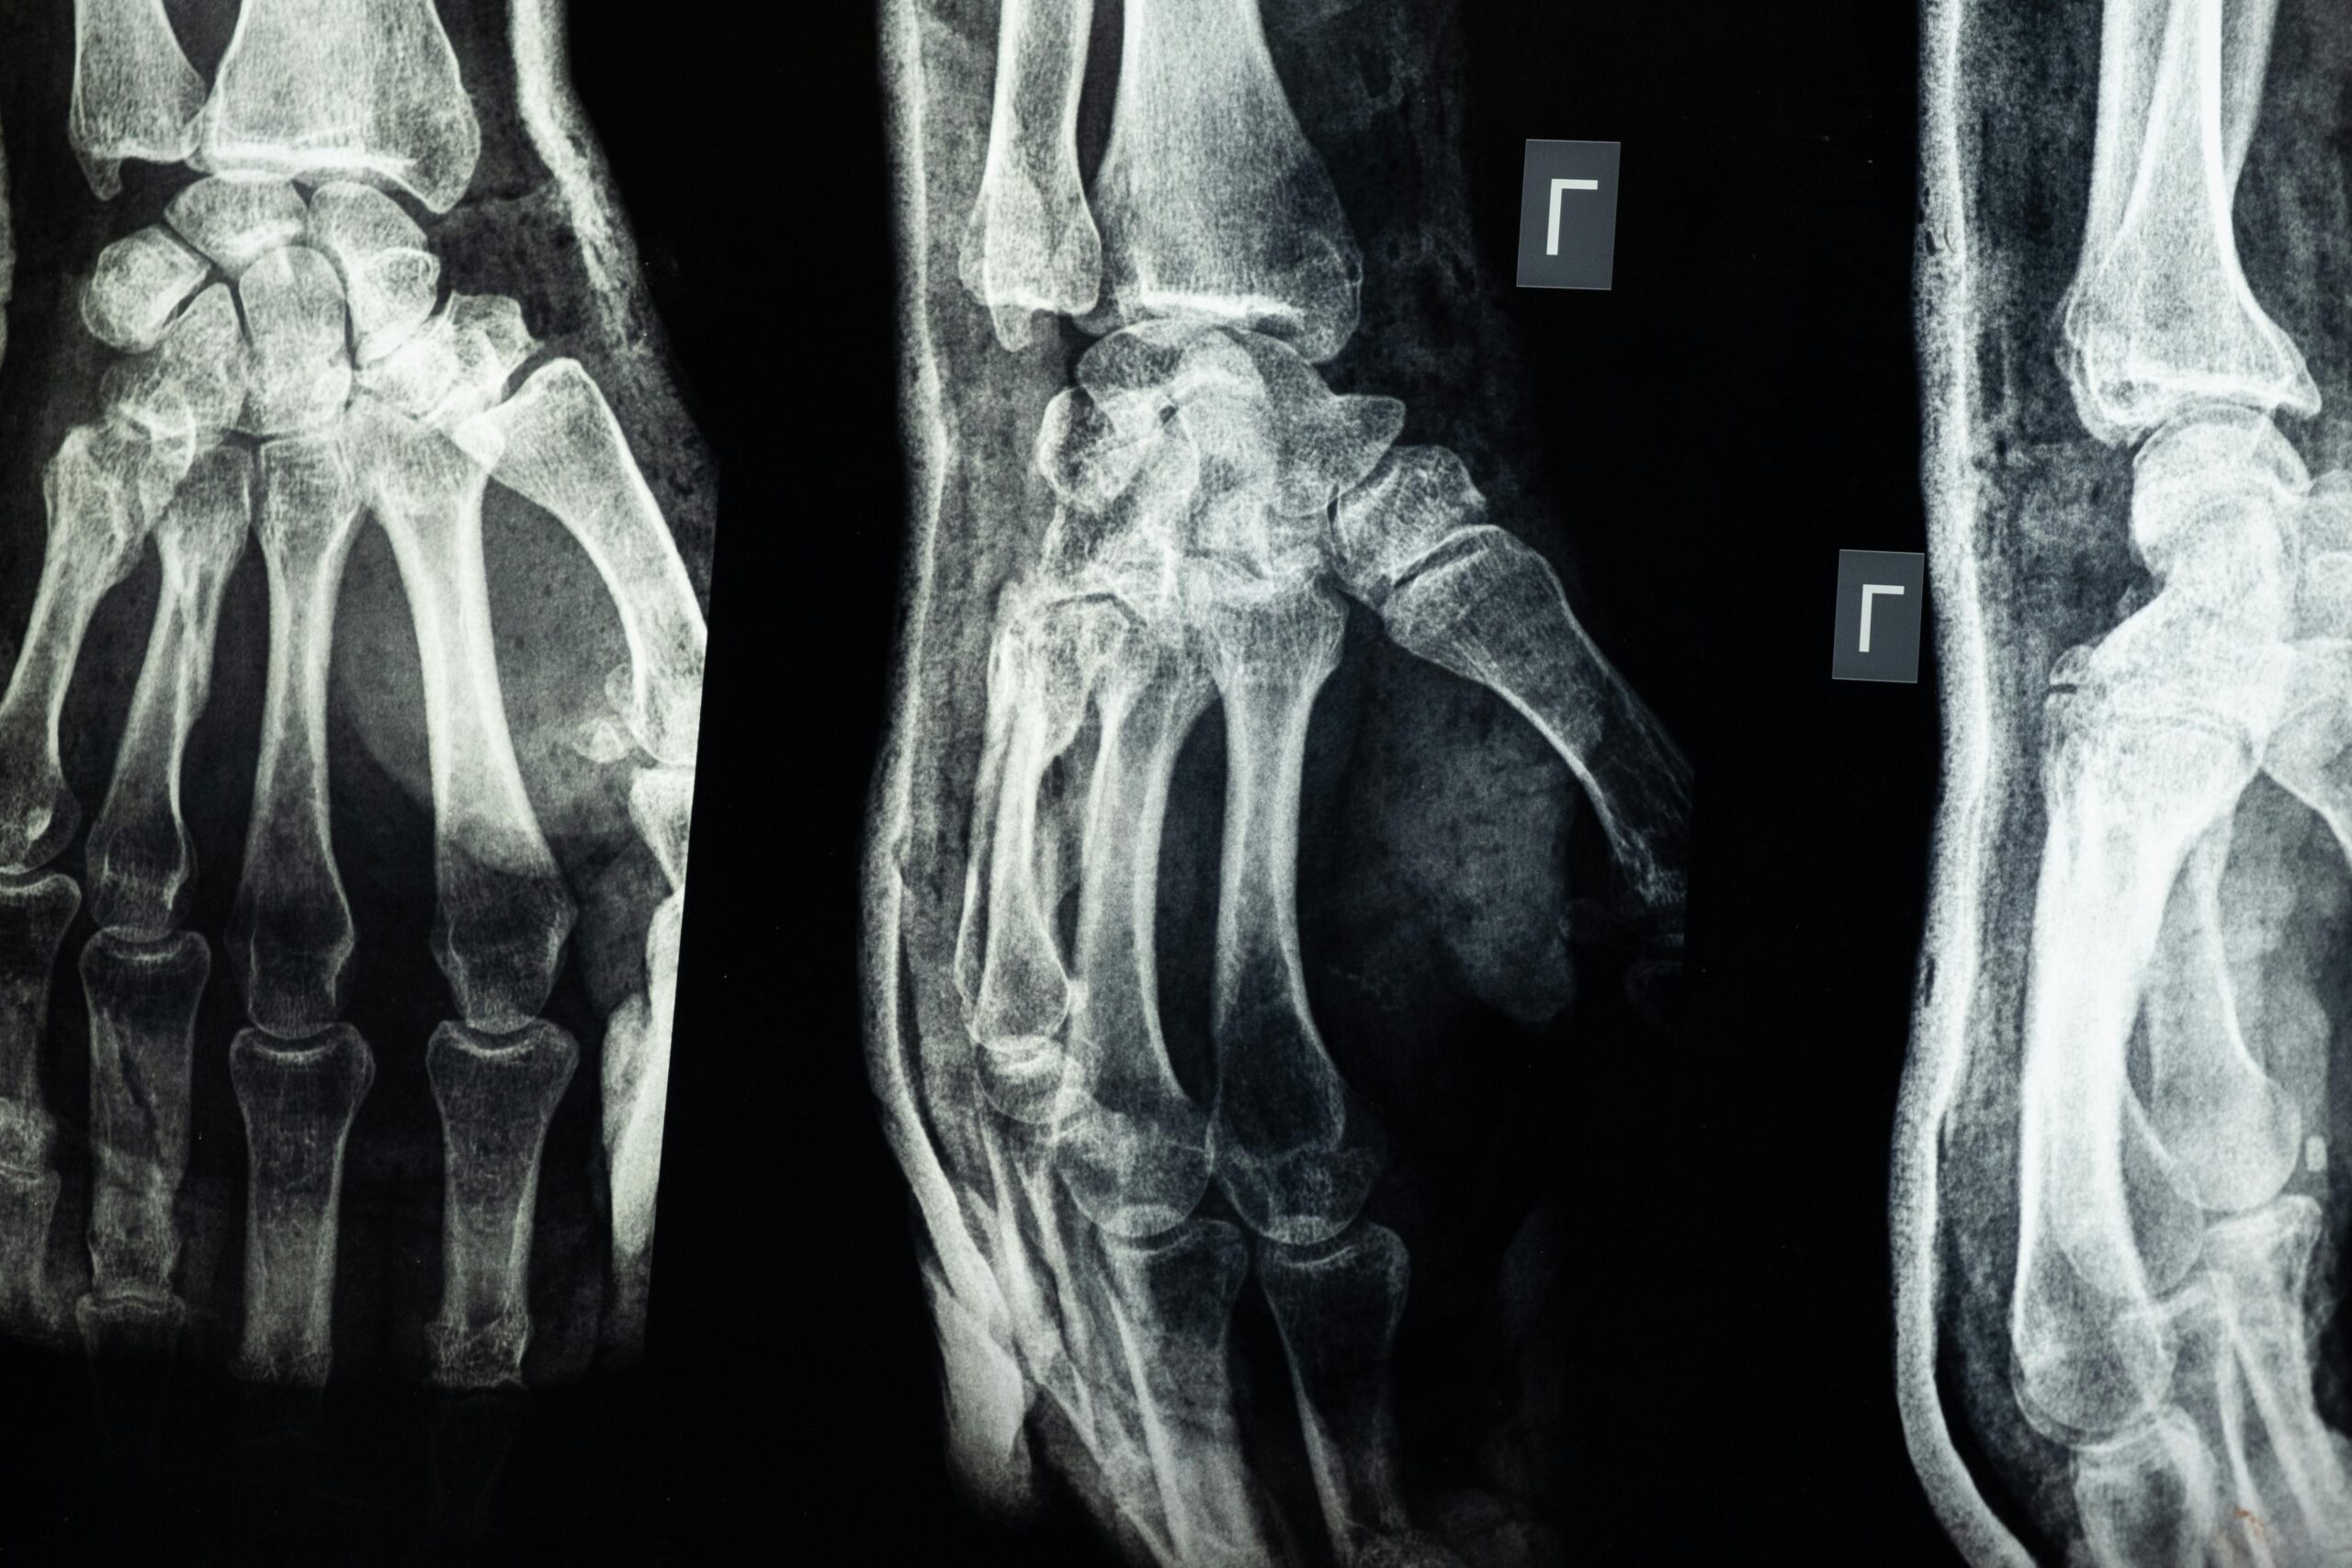

Many acute injuries occur as a result of a traumatic event. An acute ankle sprain can occur because of a specific event such as the ankle dorsiflexing (pointing up) while the foot plantarflexes (points downward). An acute finger sprain can occur when an object falls onto the finger. A fracture of a bone can occur if a person falls and lands on the bone. Acute injuries that occur as a result of an event are typically understood by the person who is injured and the people who witnessed the event. The time when the injury occurred is known. The event that produced the injury occurred in the present. The event that occurred to produce the injury is typically remembered.

Trauma of sudden onset can lead to an overload to varying extent to a tissue surface that has not had the opportunity to adapt. The muscle, ligaments, tendons and joints can be overloaded in a matter of seconds. Due to the rapid development of symptoms such as swelling, pain and decreased function, it is often easy to diagnose the injury.